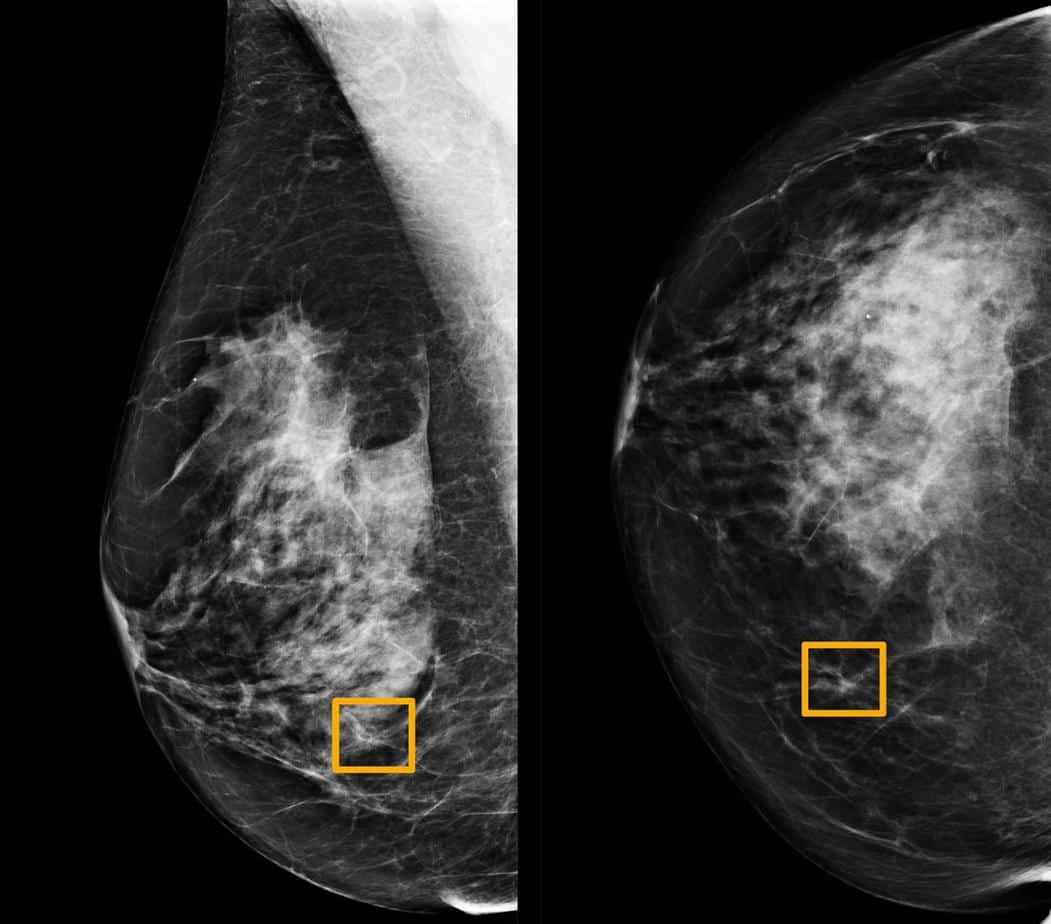

Telset.id, Jakarta Ā ā Ahli radiologi menyebut, sistem kecerdasan buatan atau artificial intelligence atau AI Google bisa membantu deteksi kanker payudara lewat screening mammogram. Bahkan, akurasinya dinilai sangat tinggi.

Seperti dilansir Reuters, dalam studi yang diterbitkan di jurnal Nature pada Rabu (1/1/2020) waktu setempat, AI Google memiliki potensi untuk meningkatkan akurasi skrining kanker payudara yang diidap oleh banyak perempuan.

Seperti dikutip Telset.id, Kamis (2/1/2020), tim para ahli, termasuk peneliti di Imperial College London dan National Health Service Inggris, melatih sistem itu untuk mengidentifikasi kanker payudara ke puluhan ribu mammogram.

Mereka kemudian membandingkan kinerja sistem dengan hasil aktual dari 25.856 mammogram di Inggris dan 3.097 di Amerika Serikat. Studi menunjukkan, sistem AI dapat mengidentifikasi kanker dengan tingkat akurasi tinggi.

Keakurasiannya sama dengan ahli radiologi. Fakta tersebut membantu mengurangi jumlah hasil positif palsu sebesar 5,7 persen untuk kelompok berbasis di Amerika Serikat dan 1,2 persen untuk kelompok berbasis di Inggris. [SN/HBS]